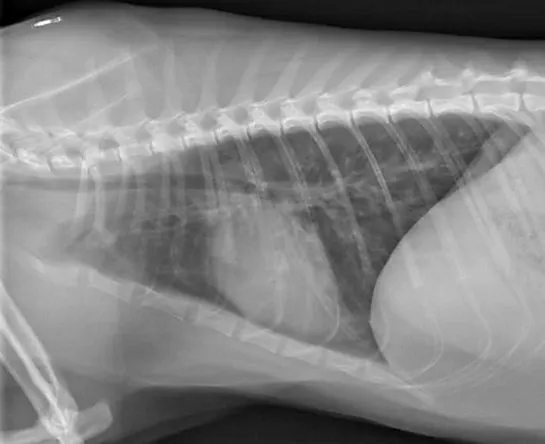

Obstructions of the upper airway (ie, nasal cavity, pharynx, larynx, trachea) typically cause respiratory distress, cyanosis, and loud breathing or goose-honking. Dogs may be concurrently hyperthermic because of a reduced ability to pant and dissipate heat.6 Diseases and/or conditions that commonly cause upper airway obstruction include severe allergic reactions (eg, bee stings), brachycephalic obstructive airway syndrome, laryngeal paralysis, and tracheal collapse (Figure 1).

Featured Image

FIGURE 1

A Yorkshire terrier intubated for emergency treatment for severe tracheal collapse

Emergency management of upper airway obstruction involves administration of supplemental oxygen (via flow-by, mask, or cage) and sedation (eg, butorphanol [0.2-0.4 mg/kg IV/IM] and/or acepromazine [0.01-0.02 mg/kg IV/IM]). In addition, short-term administration of anti-inflammatory doses of corticosteroids can help reduce inflammation and obstruction.7 In severe cases of upper airway obstruction, emergency intubation, or tracheostomy if intubation is not possible, may be necessary.